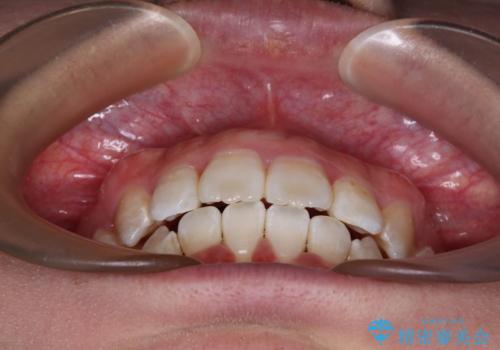

唇からはみ出るほど飛び出した前歯 ワイヤー装置による抜歯矯正

- 飛び出した上顎の前歯と八重歯を気にして来院された患者様です。

口元を積極的に引っ込めるために、上下左右の小臼歯計4本を抜歯することとしました。

下顎前歯の歯肉が元々薄く、歯肉退縮リスクがあったため、細心の注意を払って治療を進めましたが、残念ながら1歯退縮を起こして歯根が露出してしまいました。

今後、患者様と相談しながら、歯肉移植を行っていく予定です。